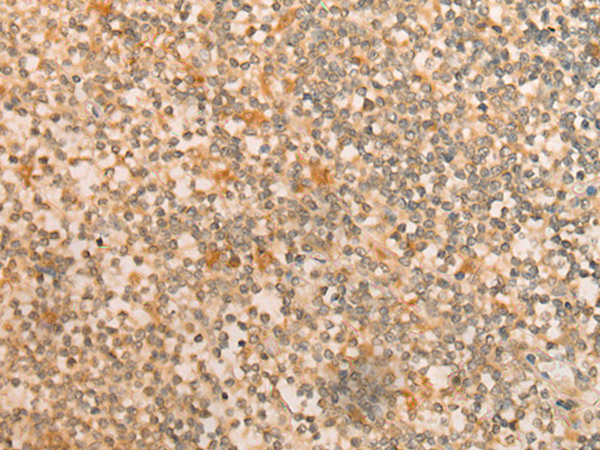

分类: 科研抗体货号: P02476别名: T3G; IMD17; CD3-GAMMA应用: WB反应种属: Human, Mouse